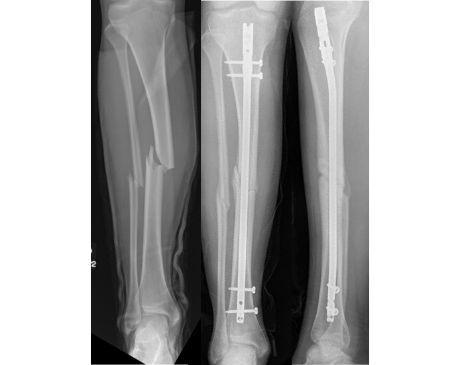

I was hit by car, had a compound fracture with a bone sticking out of my left foot. Broken tibia and fibia?. Screwed plate and bones back together. I am healing fine, next visit 3/26 to remove stiches. I seem to have total function of foot. Still have 2 more weeks of not using leg, but very hopeful.